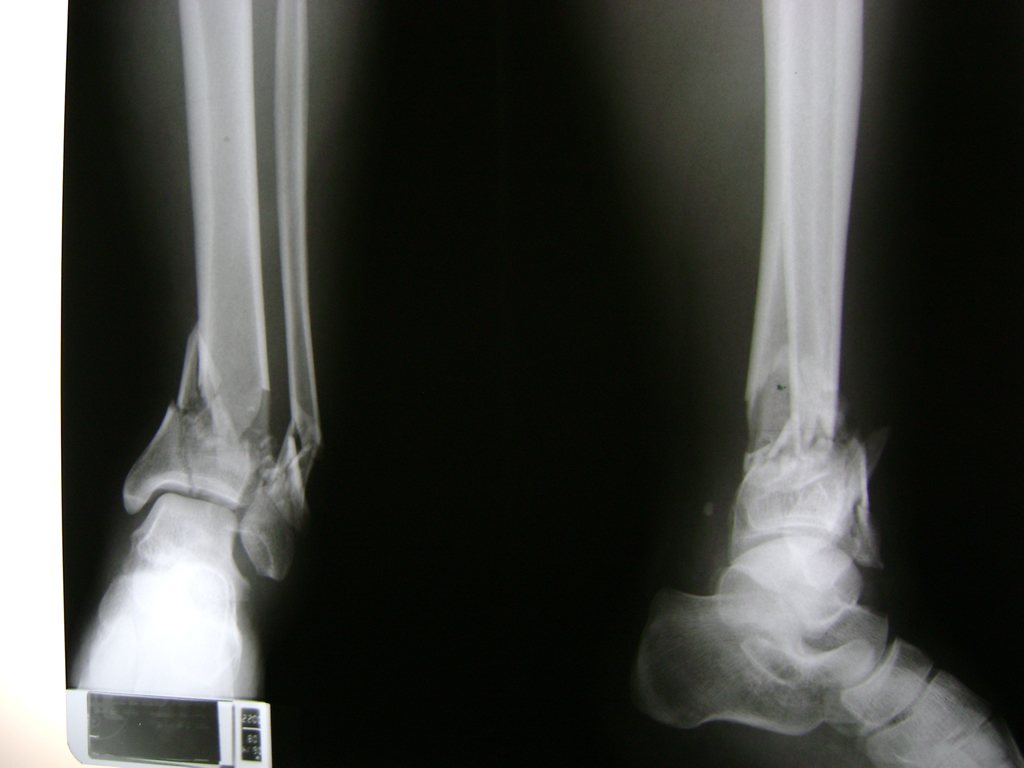

Una fractura de tobillo es la rotura de uno o más de los huesos del tobillo. Estas fracturas pueden ser:

Algunas fracturas de tobillo pueden requerir cirugía si:

- Los extremos de los huesos están desalineados entre sí (desplazados).

- La fractura se extiende hasta la articulación del tobillo (fractura intra-articular).